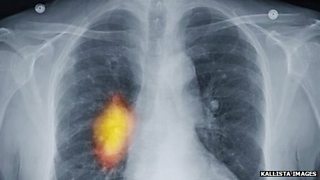

Susan Short and Ed Jones discuss potential new treatments for brain tumours.